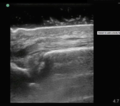

Normal

- Longitudinal views show continuous densely striped parallel lines

- Transverse views show oval structure with punctate interior